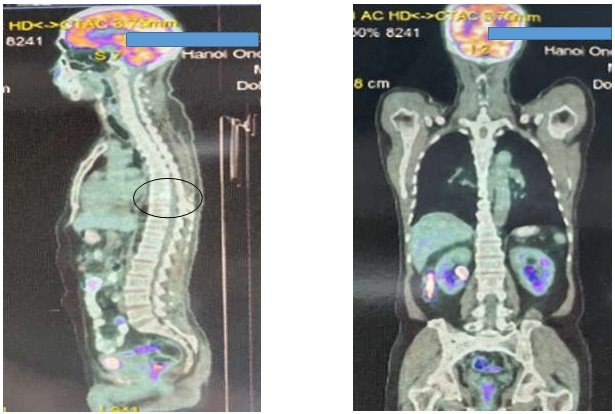

Hình ảnh chụp PET/CT sau 6 chu kỳ điều trị MD + Hóa trị (07/2022): Hình ảnh đặc xương ở thân đốt sống D8, tăng chuyển hóa FDG (SUVmax: 2,46; giảm chuyển hóa FDG so với phim chụp ngày 25/1/2022).

Hình 2: Ảnh chụp PET/CT sau điều trị

So sánh kết quả trước và sau điều trị (hình 3): như vậy, sau điều trị bệnh đáp ứng một phần

Hình 3: Kết quả PET/CT trước và sau điều trị